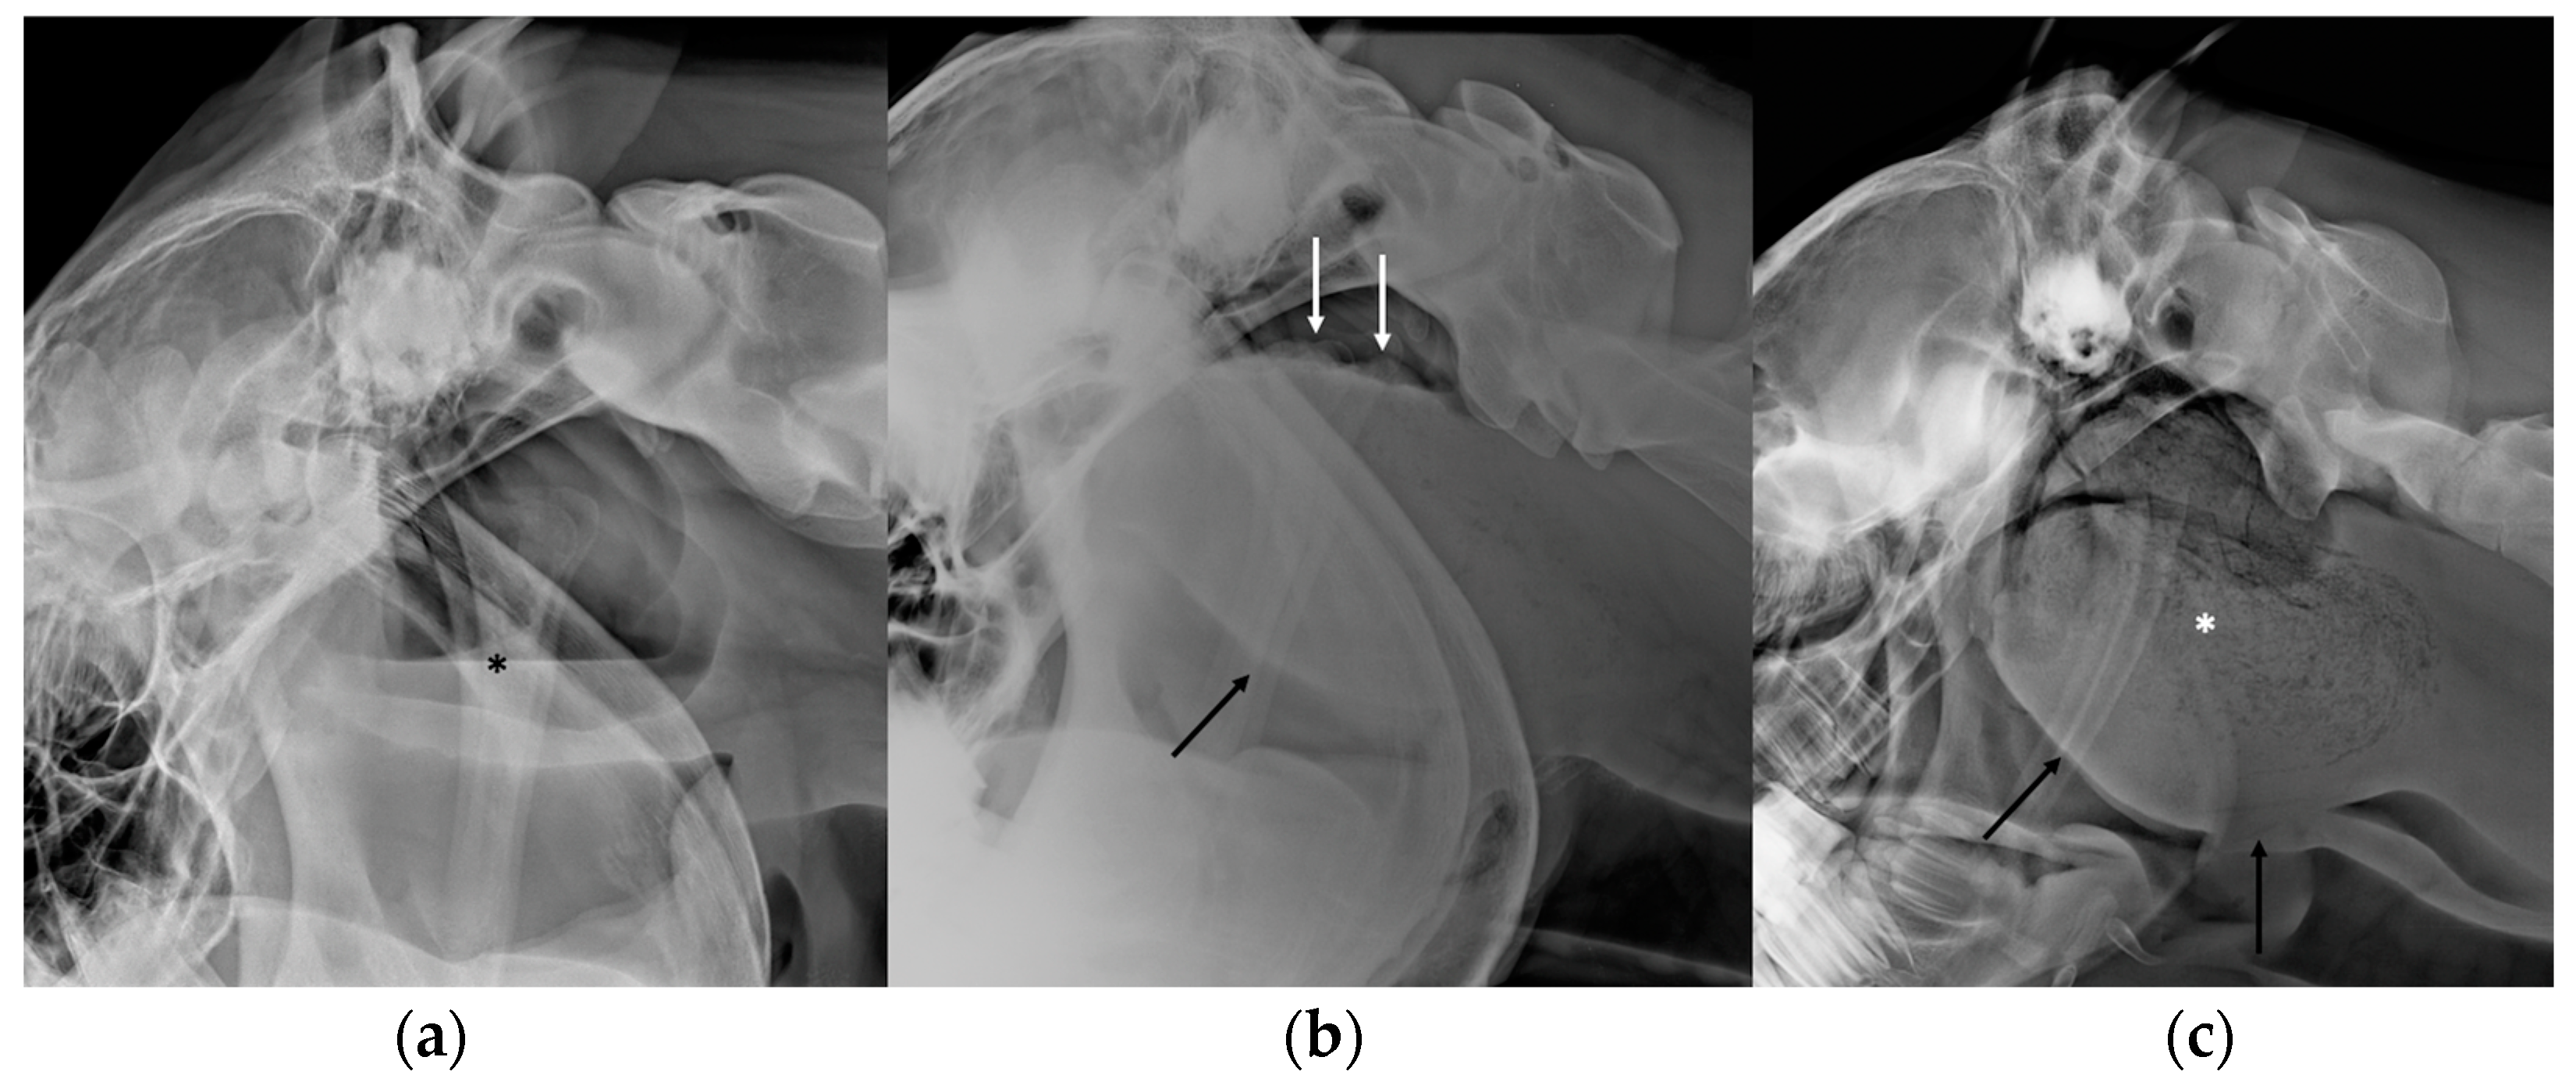

2.1. Radiography

3.2. Guttural Pouch Tympany

3.3. Guttural Pouch Hemorrhage